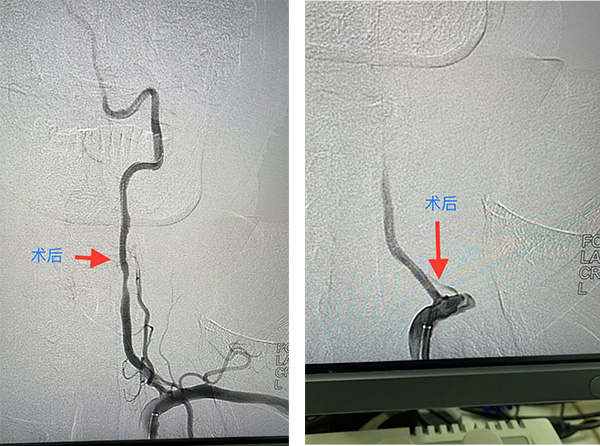

术后DSA

heheng2321a.jpg

入院后的第15天,马明辉医生为患者在局麻下行经皮左椎动脉狭窄处血管成形术及支架置入术。整个手术患者都处于清醒状态,术后自诉症状得到了明显改善。术后第二天,解除压迫器后,患者就可以轻松的下地行走了。出院时李先生激动的握着马医生的手:“谢谢马医生,手术整个过程我都是清醒的,一点也不难受,更没想到的是术后效果这么明显,今后再也不需要给家里人添麻烦了,我真是太高兴了。”